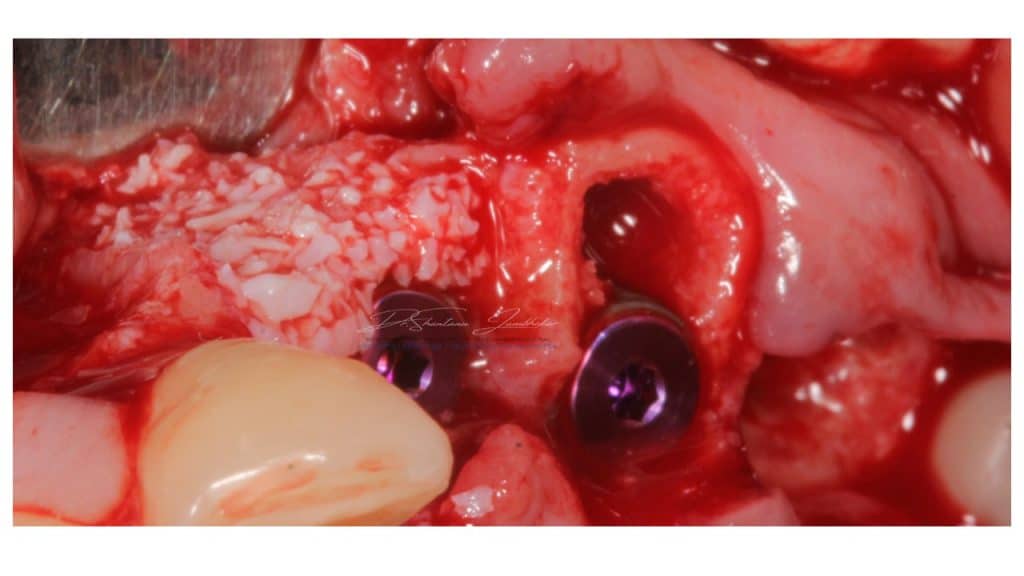

Extraction & Immediate Implant (Type I) placements were performed for site 23,24 along with Guided Bone Regeneration using Xenograft from Geistlich BioOss and GBR Membrane along with collagen fleece with two stage protocol (submerged healing with healing screws).

Conelog Progressive line Fixtures were placed 4.3X 9 at both sites. Fixtures were selected based on their variable Implant thread design and fixture morphology with active threads all the way down to the apex which offers excellent primary stability even in deficient bone conditions.

Immediate Implants (Type I) placed with site 23 & 24

Implants in situ with Mounts in Site 23,24 & 26

Covers screws connected with site 23,24 for closed healing & 26 with wide emergence custom healing abutment